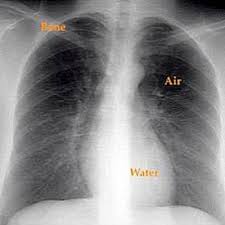

Bisa dibilang, kondisi ini bukanlah penyakit, tetapi perwujudan dari beberapa penyakit paru yang mungkin menyerang anda. Punca paru paru bocor @ pneumothorax. Jenis bendalir tersebut adalah bedasarkan punca penyakit iaitu sama ada jenis exudate (bendalir yang mempunyai kandungan protein tinggi) atau tansudate (berair). Mulai dari batuk, sesak napas, nyeri, perubahan suara, lelah, bengkak, dan masih banyak lagi. Tbc.asma.sembuh 100% dengan ( minyak herbal jum 1000 ) sudah tersedia di tokopedia.bukalapak.shopee.salam sehat kita semua.

Mulai dari batuk, sesak napas, nyeri, perubahan suara, lelah, bengkak, dan masih banyak lagi. Jika udara memasuki ruang pleura sama ada dengan. Mengenal penyakit paru paru basah pneumonia. Jenis bendalir tersebut adalah bedasarkan punca penyakit iaitu sama ada jenis exudate (bendalir yang mempunyai kandungan protein tinggi) atau tansudate (berair). Tanda khasnya ada pada intensitas, keparahan, dan gejala tambahannya.

Jika udara memasuki ruang pleura sama ada dengan. Infeksi akut pada paru bincang sehati. Keadaan ini berlaku kerana berlakunya kecederaan pada permukaan. Posted by ummuziyad on august 9, 2017 in no comments. Masalah jantung (cardiogenic pulmonary edema). Jenis bendalir tersebut adalah bedasarkan punca penyakit iaitu sama ada jenis exudate (bendalir yang mempunyai kandungan protein tinggi) atau tansudate (berair). Istilah ini biasanya digunakan masyarakat umum untuk. Bisa dibilang, kondisi ini bukanlah penyakit, tetapi perwujudan dari beberapa penyakit paru yang mungkin menyerang anda.